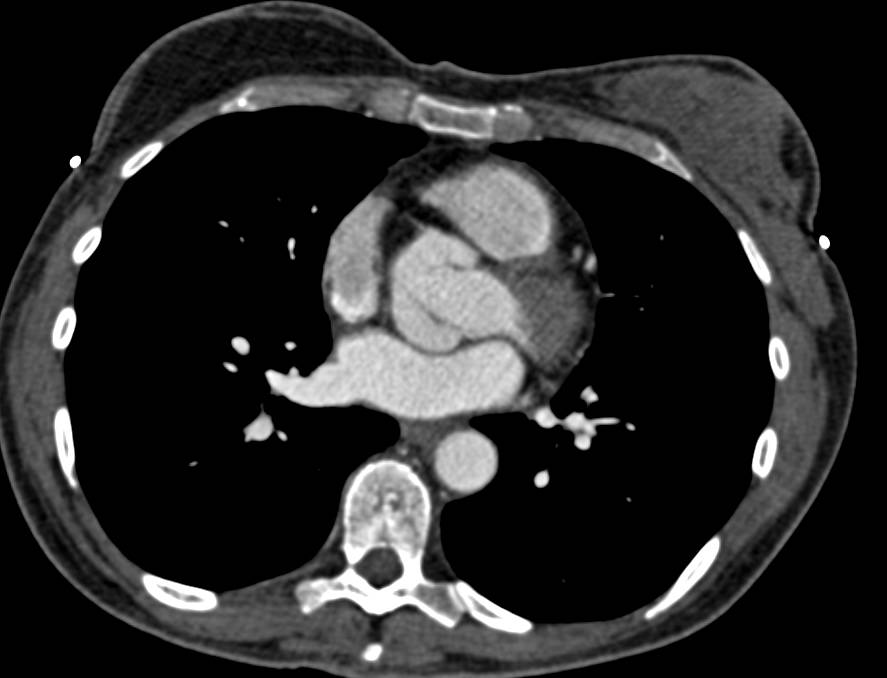

Vascular Mapping for Gluteal Perforators